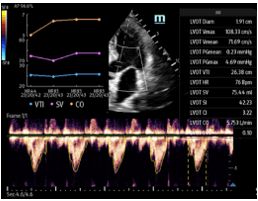

Figure D. In image D1, the TE7 Ultrasound machine is looking at the inferior vena cava (IVC). Image D2 shows the lung with ultrasound and D3 shows a cardiac assessment with smart measurements to check heart function. Images courtesy of Mindray Medical International.

Automated Velocity Time Integral (VTI) and Cardiac Output (CO) measurements enable rapid cardiac function assessment. This software automatically locates the color box and Pulse Wave (PW) Doppler sample line in real-time. A graph of parameter trends for CO, Stroke Volume (SV), and VTI is produced to guide decision-making.